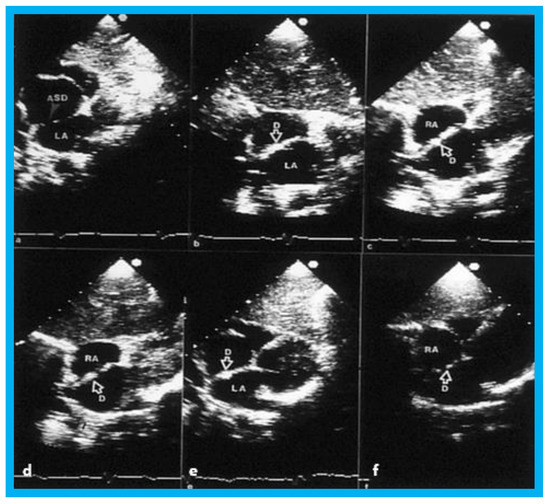

In group I (14 subjects with left-to-right shunt), the Qp:Qs fell from 2.1 ± 0.5 to 1.08 ± 0.2 (p < 0.01) following ASD closure. The RV dimension decreased from 2.3 ± 0.6 to 1.7 ± 0.3 cm after occlusion (p < 0.01) and stay diminished (1.6 ± 0.46 cm) at latest follow-up evaluation (Figure 8, left panel). The left ventricular (LV) end-diastolic dimensions did not change (Figure 8, right panel). Paradoxical or flat inter-ventricular septal motion was seen in 11 of 14 patients (79%) prior to ASD occlusion which returned to normal at follow-up (Figure 9). Device position was stable (Figure 10) in all patients.

Small to trivial left-to-right shunts across the atrial septum were seen by color-Doppler in six of 14 patients (43%) the day after ASD occlusion, and trivial shunts persisted in three of fourteen (21%) patients at follow-up. Two of these children had cardiac catheterization one year following device implantation, and no left-to-right shunt was found by oximetry and no shunt was detected on levo-angiographic phase of the pulmonary artery cineangiogram. Generally, small shunts became trivial and trivial shunts disappeared during follow-up. None of the patients had clinical signs suggestive of ASD, and no patient needed surgical closure during this period.

Figure 10. Selected video frames from 2D echo studies in subcostal position of the atrial septum in long-axis view prior to (a); immediately after (b); and at one (c), six (d), 12 (e), and 24 (f) months following atrial septal defect (ASD) closure illustrating the results of transcatheter closure of ASD with buttoned device. Note the position of the device (D) across the ASD (bf) during follow-up, the device appears to be incorporated into the atrial septum. On pulsed and color-Doppler studies concurrent with two-dimensional echo studies, there was no evidence for left over shunt (not shown). LA, left atrium; RA, right atrium. Reproduced from Rao P.S., et al. [9].